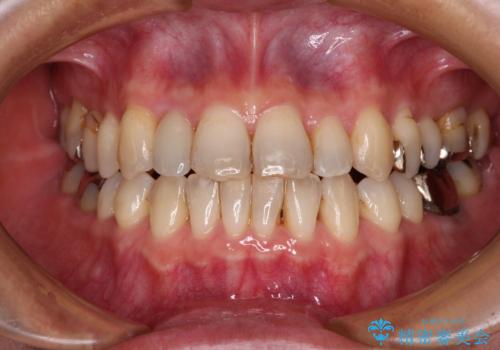

- 中学生の時にスポーツで折ってしまった前歯が変色してしまったとのことで来院された患者様です。

結婚式に向けてオールセラミッククラウンにて仕上げていくこととしました。

既にクラウンが装着されていた歯は歯根の先端に病変が認められたため、根管治療を行うこととしました。

仮歯装着の時点で自然な見た目となり、オールセラミッククラウンを装着した際には、まるで自分の歯のようと喜んでくださいました。